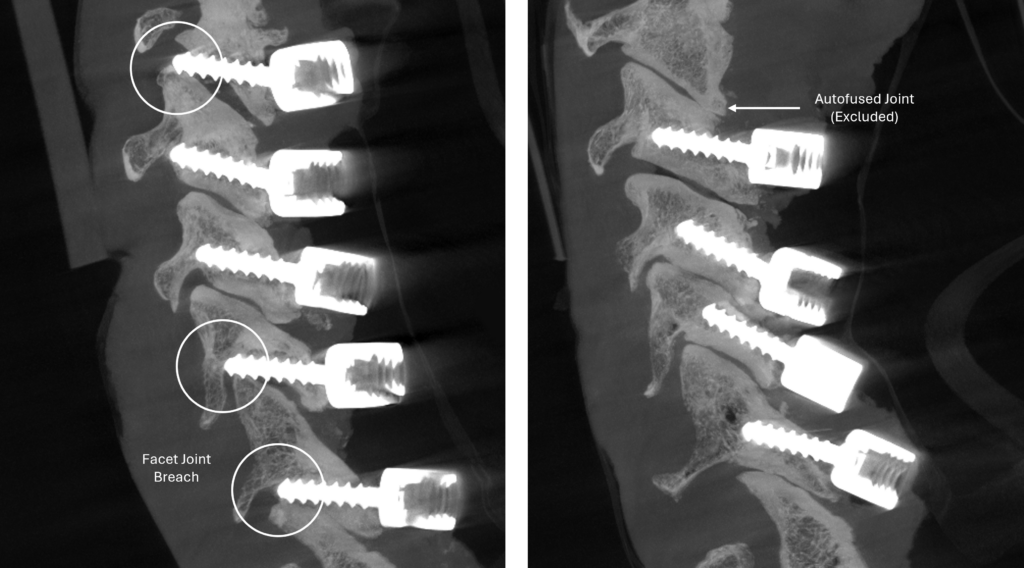

Lumbar Spine: FLASH Facet Fusion

Navigated MIS procedures for lumbar spinal fusion have grown as navigation systems become more readily available. Fusion in MIS presents unique challenges to surgeons due to limited visibility and access to the posterior elements.

FLASH™ Facet Fusion is a navigation-compatible system that accesses the facet joints and acts as a working channel for the entire facet fusion procedure. FLASH Facet Fusion Instruments and FLASH Facet Pellets offer surgeons a technique to reproducibly locate, decorticate, and fuse in minimally invasive lumbar procedures.

Locate

Seamless integration with 7D FLASH Navigation

Real-time tool projection provides a geometric representation of the Lumbar Inserter to help target the facet joints

Decorticate

The navigated Lumbar Inserter guides the Facet Drill during decortication

- Inserter forks center cannula on the joint line

- Enables equal decortication of superior and inferior facets

- Drill creates a contained defect within the inserter forks

- Inserter designed to control drill depth